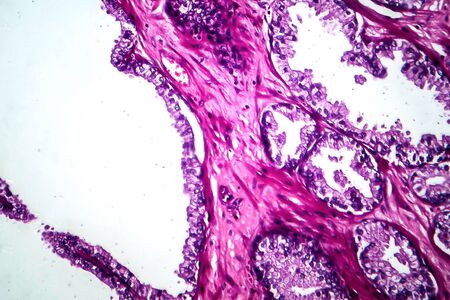

Bowen's Disease Tumor under the microscope 100x